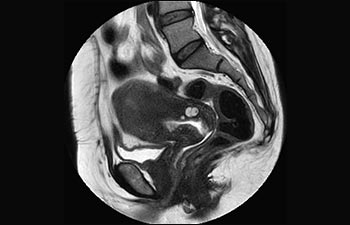

Enhanced diagnostic confidence in neuro oncology